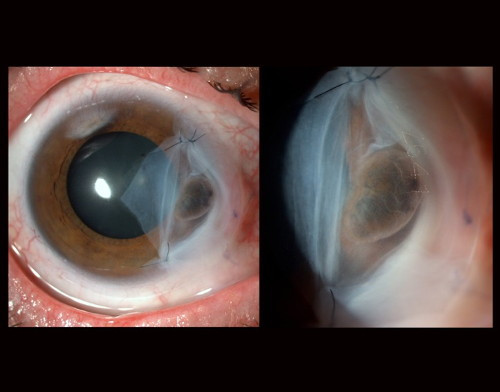

- 1. mesto v kategoriji SLIT-LAMP